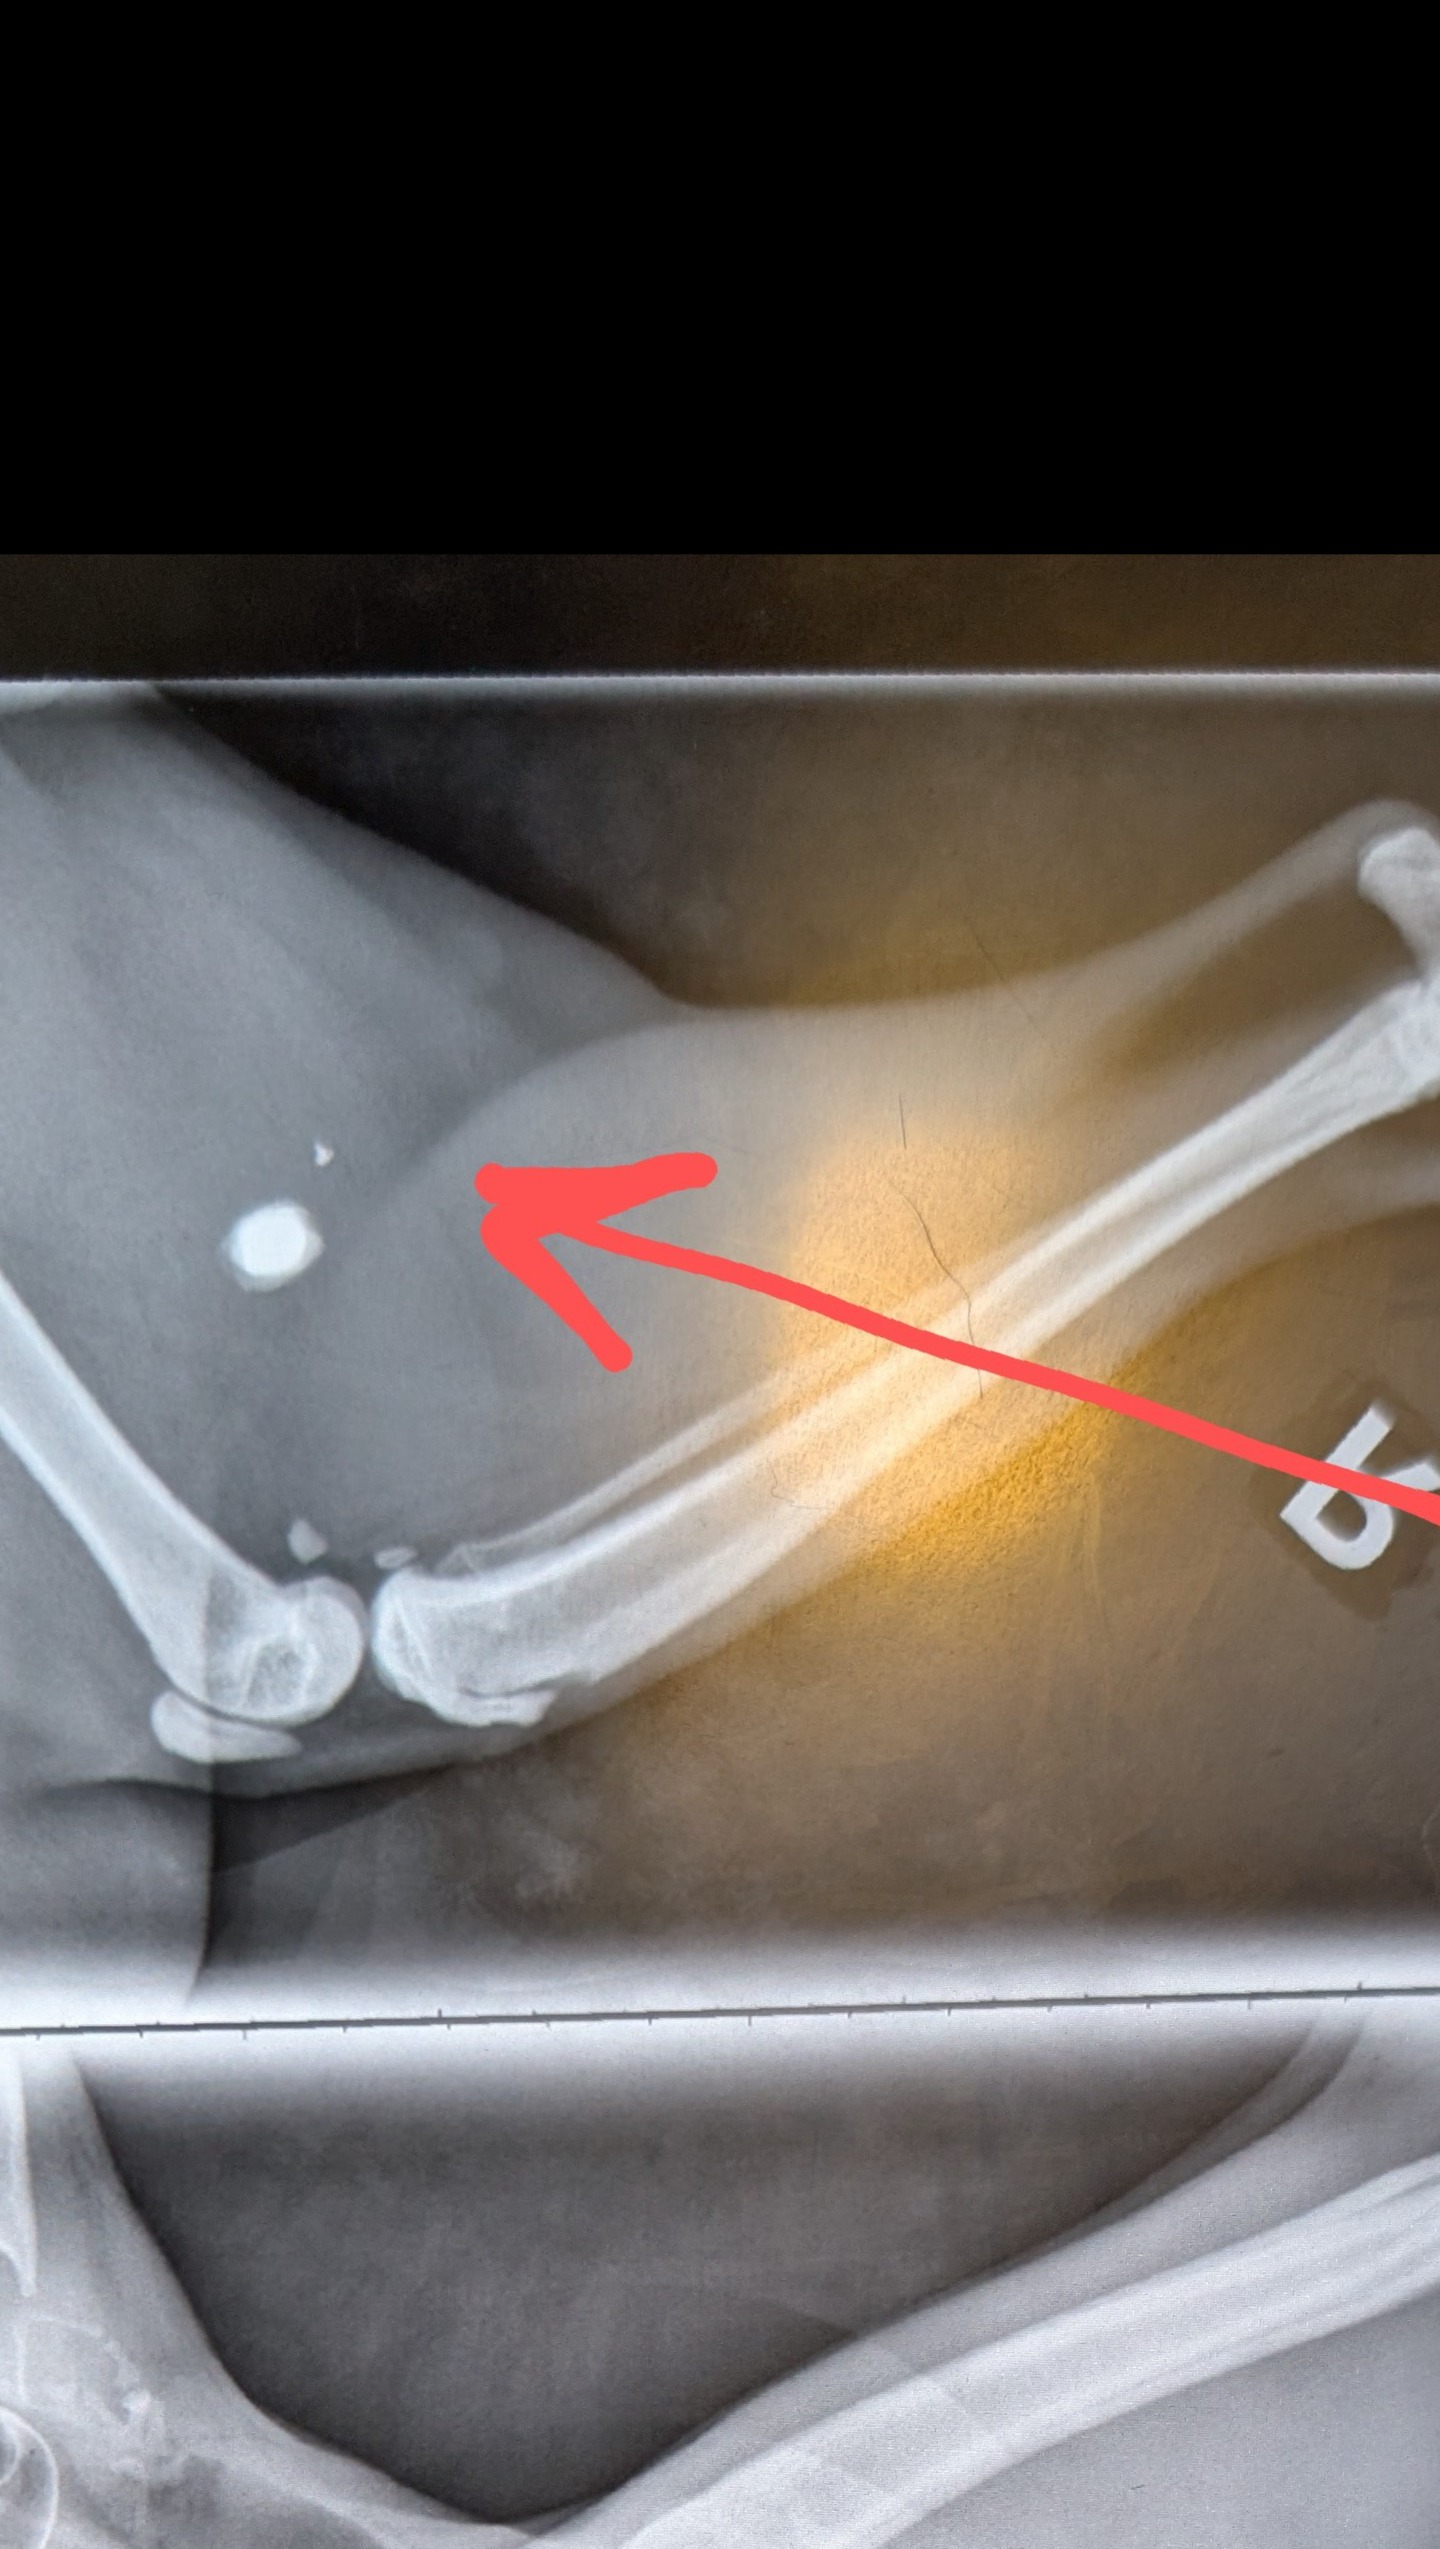

The X-rays surprised us and immediately made me tear up in horror: she had been shot with something, and there was still several pieces of metal in her body. One was buried in her back leg, close to her hip. Another was closer to her chest, but on her flank. Her paws were abraded as if she had been running or she got stuck. And she had several scratches on her face. She had not eaten in too long and her vitals suggested she was approaching shock if she wasn't already there.

The vet stated that the pellet wounds seemed several hours old, possibly from the night before. The scratches and abrasions weren't as great of a concern. We waited. And waited.

Miraculously, through 1 surgery and 3 days in patient, she recovered well. The metal pellets, seemingly from a pellet gun, missed any vital organs or arteries. After several days inpatient, somehow, her spirit carried her through. The scrapes and cuts have been healing, her vitals are stable and strong, and her fur is in the very beginning stages of growing back over her shaved spots.